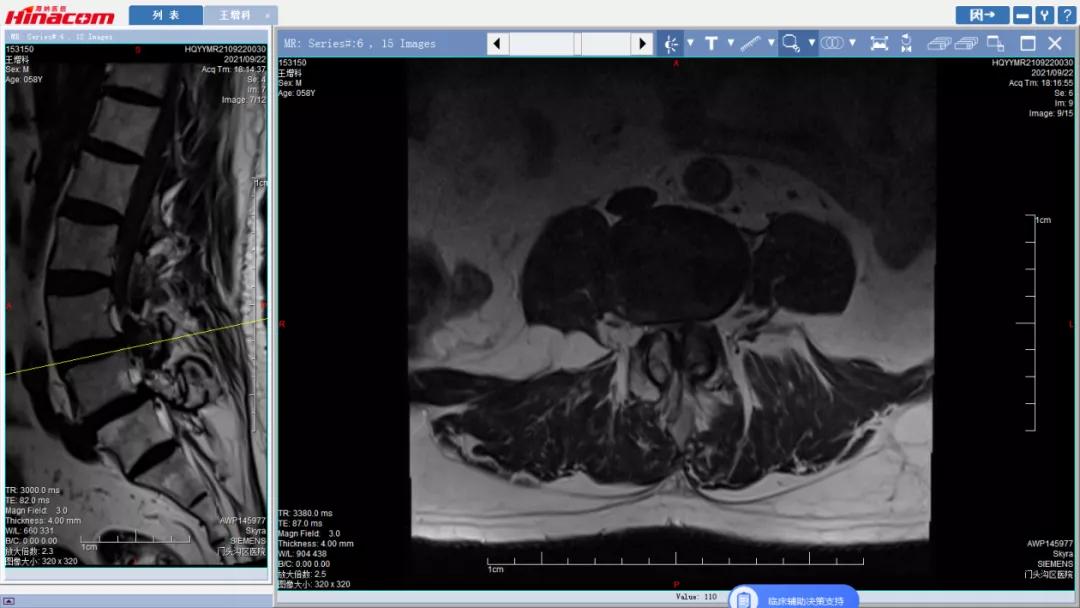

腰椎管矢状面--术前MRI

腰34椎管水平面--术前MRI